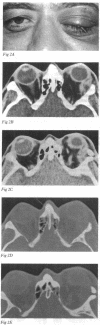

Periorbital dermoid cysts should be removed because they commonly leak their irritant contents into the surrounding tissues. The underlying bone may, however, be involved in patients with dermoid cysts at the outer canthus. Computed tomography studies of 70 patients (43 men and 27 women, aged 30 months to 63 years, mean 29 years) with proved dermoid cysts of this type were reviewed. The lesion was always unilateral; 34 were on the left. The bone of the lateral wall and superotemporal angle of the orbit showed the following abnormalities, often in combination: pressure erosion in 61 cases and an otherwise abnormal shape, probably developmental, in 55; the dermoid cyst entered a tunnel or canal through the lateral wall in 24; a blind pit or crater in 15; and a cleft in 20; many patients also showed abnormal bone texture. These findings are extremely important for planning adequate surgery, and indicate that bony involvement is much more frequent than previously appreciated.